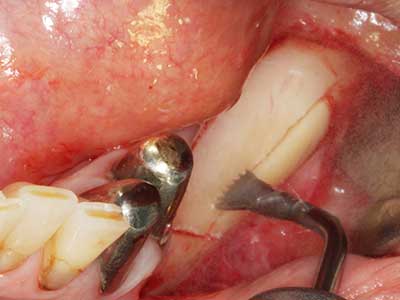

Piezo surgery has additional advantages when harvesting bone blocks. In addition to the high precision with osteotomy described above, the use of the thin saw tips specifically minimizes loss of material. Greater loss of material during harvesting can be expected with the thicker instrument tips, particularly when using Lindemann drills (Lakshmiganthan, Gokulanathan et al. 2012). The basal separation, which is necessary particularly for retromolar block transplants, is simplified by specially designed rectangular saws, with the result that piezo surgery is viewed as a precise, simple and safe procedure for harvesting retromolar bone blocks (Happe 2007) (Fig. 1-12).

When surgical procedures are performed on bone in the immediate vicinity of sensitive structures such as blood vessels or nerves, rotary instruments pose a significant risk of iatrogenic injury. Piezoelectric devices can be helpful for preparation of bone covers and removal of hard tissue close to nerves, particularly for exposure of nerves after iatrogenic injury but also during nerve lateralization for resective and reconstructive procedures or implant placement (Fig. 17-20). Light contact between the piezotip and the nerve does not generally result in damage but proceeding incautiously with saw-like motions or attachments where a residual bone substrate remains may cause temporary or even permanent nerve damage. However, the risk of damage is considered to be substantially lower than when using saws or milling instruments (Pereira, Gealh et al. 2014).